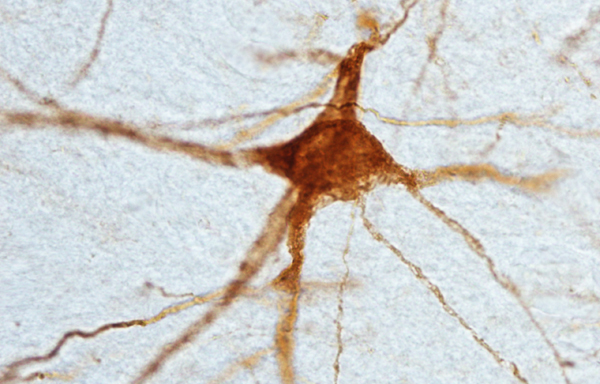

Stem cell implants for Parkinson’s show promise in monkeys

Specialized human stem cells can mature in the brains of monkeys with a Parkinson’s-like disease. That finding, presented October 15, suggests that stem cells may be able to replenish dying brain cells in people with Parkinson’s. Three months post-transplantation, the human cells seemed to be flourishing in rhesus monkeys’ brains. The cells assumed the triangular shape of neurons and sprouted long, elaborate projections that send and receive messages. “We were just blown away when we saw these cells,” said study coauthor Dustin Wakeman of Rush University Medical Center in Chicago. Observations suggested the cells produce the brain chemical dopamine, just like the cells that are destroyed in people with Parkinson’s.